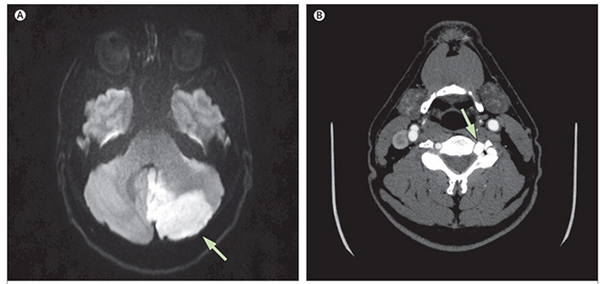

小脑梗死的MRI表现

需要说明的是虽然部分后循环缺血会引起孤立性眩晕的症状,但绝大部分的不伴有脑部症状的孤立性眩晕并不是脑梗死所致。尤其需要注意的是,颈部血管超声、TCD等检查提示的“血管狭窄、椎基底动脉供血不足”等检查结果,并不是诊断后循环缺血的依据,而且在正常人群中约

15%的人存在一侧椎动脉变细现象。因此,可以这样说,临床绝大部分眩晕发作与脑血流无关,而且“脑供血不足”这个诊断目前已被医学界废除。所以,请您不必因一份这样的TCD或颈部血管超声的报告而过分担忧。如我们考虑存在后循环缺血的可能性,我们将会根据需要为您预约头颅MRI检查。